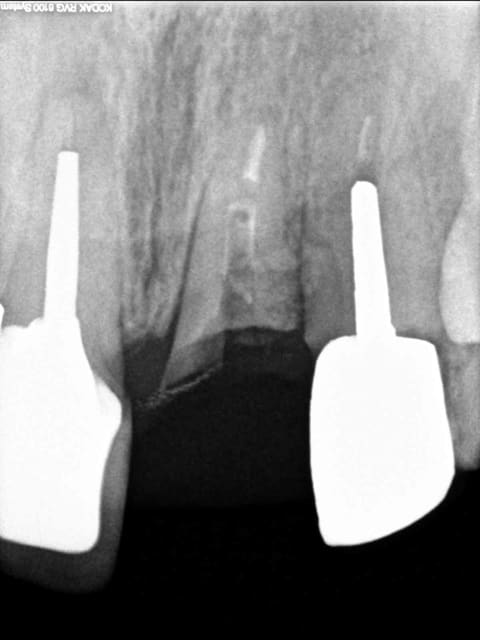

fracture d'une racine 21, infection vestibulaire

1 vue clinique

2 provisoire réalisée avec empreinte de la patiente en ayant retiré la couronne (histoire d'avoir la forme exacte de la gencive le jour de l'extraction)

3 et 4 fendu = foutu !

5 oups ... même photo.

6 RTR en place mais extraction du pan vestibulaire seulement pour avoir un site non infecté et une gencive cicatrisée (donc plus facile à suturée)le jour de la pose de l'implant.

7 dent provisoire maintenant la gencive en place.

ma question;

auriez vous extrait la dent dans sa totalité tout de suite en implantant immédiatement avec les risques infectieux? ou alors extraction, cicatrisation (et donc perte du volume gingivale) puis implantation?

voici la radio

Radio 21 fractur e kbb2or - Eugenol